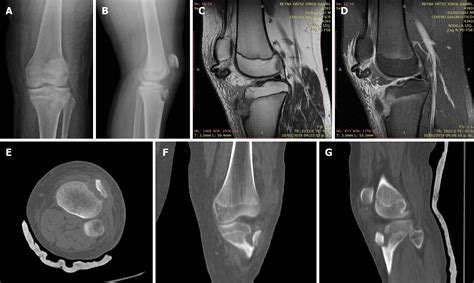

To confirm the diagnosis, medical professionals typically utilize imaging studies. X-rays are the gold standard for visualizing the displaced bone fragment and determining the severity of the fracture. In more complex or comminuted cases, an MRI may be ordered to assess the condition of the surrounding soft tissues, including the patellar tendon and menisci.

Orthopedic surgeons often categorize these injuries based on the Ogden classification system, which helps guide treatment decisions. This classification ranges from simple, non-displaced fractures to complex injuries that extend into the knee joint.

Type Severity Description Typical Treatment

Type I Small fracture at the distal part of the tuberosity. Conservative (casting)

Type II Fracture extends through the secondary ossification center. Surgery often required

Type III Fracture extends into the articular surface of the knee. Surgical intervention

However, if the fragment is displaced or if the knee joint is compromised, surgical intervention is mandatory. The surgical procedure typically involves:

• Open Reduction Internal Fixation (ORIF): The surgeon makes an incision to visualize the bone fragment.

• Hardware Placement: The loose piece of bone is secured back to the main tibia using screws, wires, or specialized anchors.